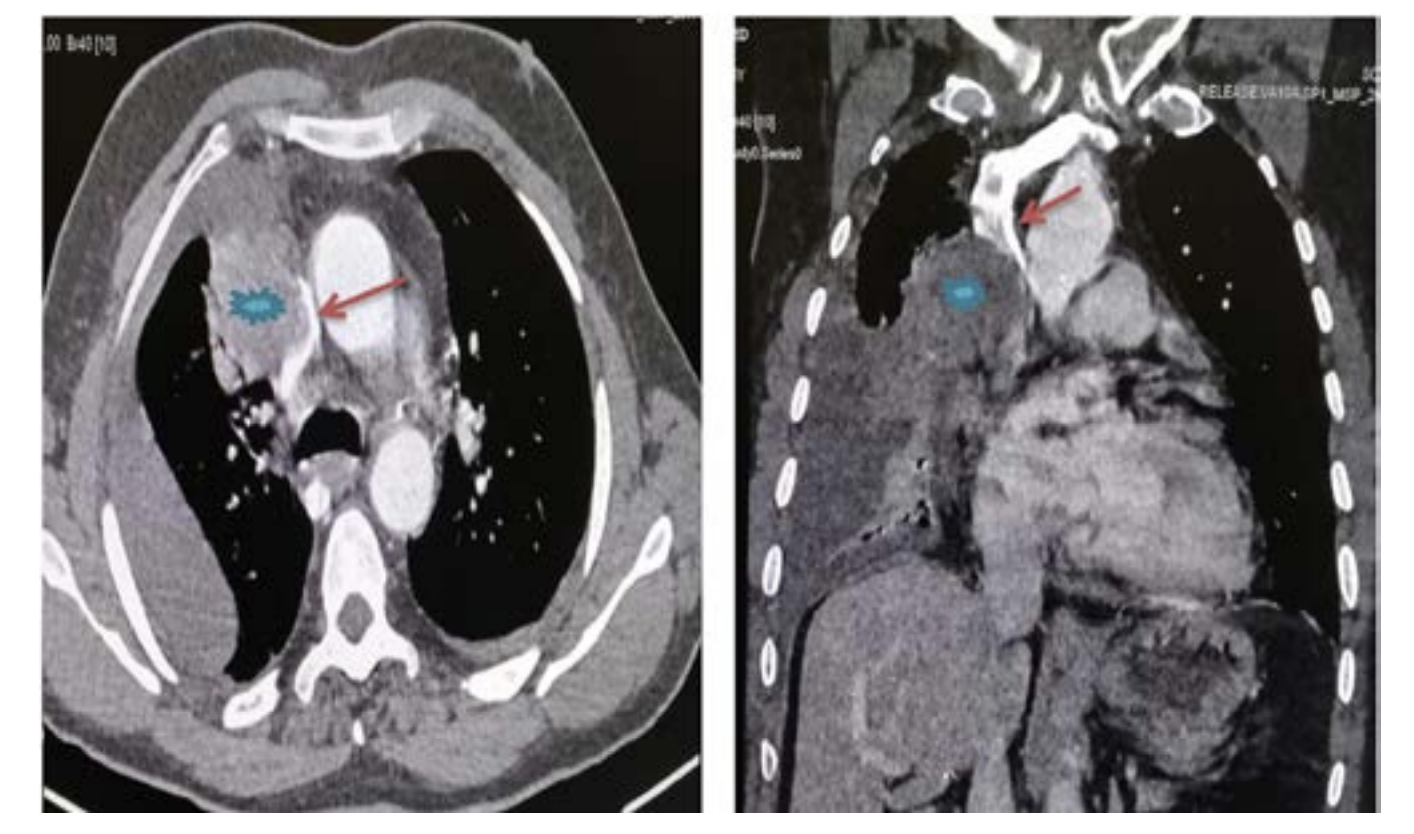

The diagnosis of SVCS is straightforward; it can be based on clinical findings. The chest CT scan is considered the main imaging tool to establish diagnosis, map, and evaluate the SVCS.5,6

The caval stenosis, in the series, was diagnosed by means of an angio CT scan of the chest, followed by confirmation using the venacavogram.

In what concerns the place of imaging exploration, the majority of authors believe that CT-scan with its high-quality multiplanar reconstructions is a crucial imaging tool. In fact, angio-CT scan confirms the diagnosis, determines the exact extent of obstruction, the nature and the degree of vena cava obstruction as well as it orients the placement of the endoprosthesis and the presence of associated pathologies.6 A venographic classification according to Stanford and Doty was set. Four Patterns of venous collateral return have been described.5 The 4th one matches with the most severe in terms of clinical symptoms (Schema 1).